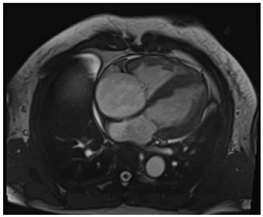

6.4. CMR Findings

CMR is a sensitive diagnostic tool for CS, with studies yielding sensitivities between 75 and 100% []. SSFP cine imaging is used to assess for regional wall thinning or thickening, aneurysmal or dyskinetic segments, and biventricular systolic function []. In CS, native T1 mapping may be focally increased in regions of fibrosis or edema []. Native T2 mapping may also be focally increased in regions of edema if there is active inflammation []. Black-blood T2 weighted imaging can improve the detection of myocardial edema and was found to have comparable diagnostic performance to FDG-PET in a retrospective study [].

The hallmark of CMR in CS is the evaluation of LGE. LGE can reflect edema in the acute inflammatory phase and replacement fibrosis in the chronic stage of CS. LGE is often patchy, mid-myocardial and/or subepicardial, and involves the basal LV segments and RV portion of the septum [,]. Sometimes, the LGE may be transmural or subendocardial, mimicking an ischemic pattern []. FDG-PET imaging complements CMR, and combining both modalities has been shown to enhance the certainty of CS diagnosis []. In a meta-analysis of histologically proven cardiac sarcoidosis, Okasha et al. found that the lack of any myocardial LGE or the presence of isolated midmyocardial, subendocardial, or transmural LGE were rarely to never present []. This highlights the potential role of certain LGE patterns on CMR in excluding cardiac involvement in sarcoidosis. Key CMR findings in CS are summarized in Table 4.